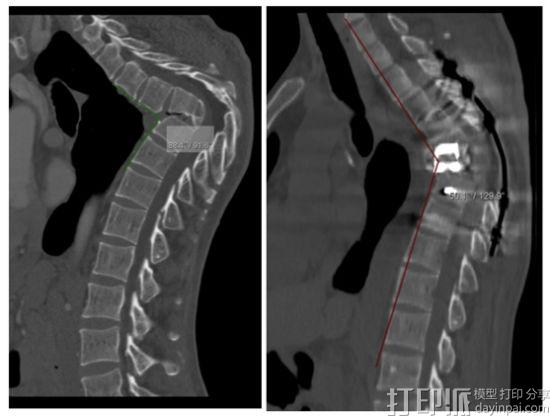

从病人方先生术前脊柱侧凸患者CT和三维重建影像来看,诊断:陈旧性胸椎结核,T5-8椎体融合,伴胸椎角状后凸畸形,胸脊髓压迫伴双下肢不全瘫。

而由于后凸非常严重,脊椎折叠约90度,且靠近主动脉,手术风险系数较高。为了提高手术的准确性和安全性,东方医院的外科团队最终决定采用3D打印来做该病例的术前规划及手术模拟。